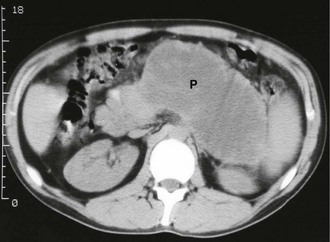

Case History

image

Fig. 25.4 Pancreatic calcification in chronic pancreatitis

This obese 55-year-old man had a long history of severe abdominal pain and alcohol abuse. Pancreatic calcification was not visible on a plain abdominal X-ray but extensive calcification is clearly seen on this CT scan